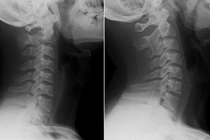

(khoahocdoisong.vn) - Việc cột sống cổ có đường cong sinh lý bình thường đóng một vai trò quan trọng nhưng lại thường bị bỏ qua. Ở nhiều bệnh nhân bị đau cổ, đường cong này bị mất đi, dẫn đến các vấn đề cơ sinh học, mà có thể dẫn đến thoái hóa các đĩa đệm và đặc biệt có thể gây giảm lưu thông máu đến não bộ.